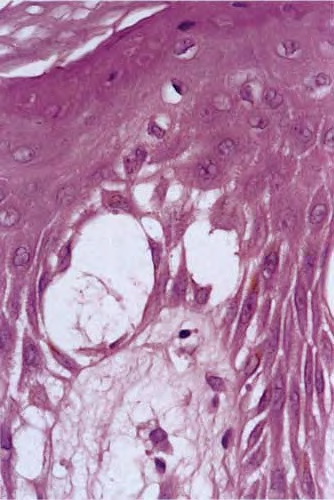

Atlas of skin histopathology